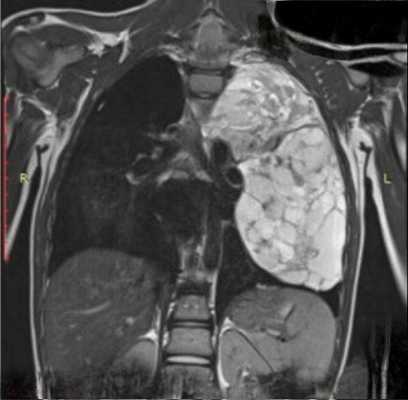

Магнитно-резонансная томография в диагностике поражений вилочковой железы

Применение магнитно-резонансной томографии (МРТ) для исследования структур грудной клетки открыло новые перспективы в прижизненной диагностике многих заболеваний.

Пульсация сердца смещает средостение во время получения изображения, что снижает ценность МРТ. Поэтому синхронизация изображения с сердечным циклом улучшает визуализацию сердца и средостения.

Сосудистые структуры средостения хорошо визуализируются на МР-томограммах ввиду того, что сигнал от просвета сосудов практически отсутствует. Вилочковая железа внутри периваскулярного пространства легче выявляется на МР-томограммах, чем при КТ. Форма, размер, интенсивность сигнала зависит от возраста. У детей вилочковая железа имеет промежуточную интенсивность сигнала, равную интенсивности сигнала от мышц или лимфоузлов. У взрослых интенсивность сигнала от вилочковой железы выше вследствие жировой инволюции, хотя она у разных людей варьирует. Размеры железы у пациентов старше 30 лет, выявленные при МРТ, лучше коррелируют с операционными находками, чем выявленные при КТ. Это связано с лучшей визуализацией инволютивных изменений при МРТ. Хотя вилочковая железа обычно располагается кпереди от крупных сосудов, она может располагаться и ретровазально. Определение локализации вилочковой железы важно для выявления связи аберрантной железы с переднемедиастинальной тимусной тканью но идентификации интенсивности сигнала.

МР-заключение о наличии опухоли вилочковой железы обычно базируется на локальном увеличении железы, выявлении связи опухоли переднего средостения с железой. Интенсивность сигнала от опухоли чаще выше, чем от нормальной ткани железы. Большинство инкапсулированных опухолей дают гомогенный сигнал как на Т1, так и на Т2-изображениях. Инвазивные опухоли чаще негомогенные на Т2-зависимых изображениях.

Хорошая визуализация сосудов при МРТ с синхронизацией позволяет выявлять нечеткость их контуров при инвазии опухолью. Перикард на ЭКГ-синхронизированных изображениях выглядит как тонкая линия, низкой интенсивности толщиной менее 4 мм. При его инвазии возможно выявление прерывистости этой линии с замещением ее высокоинтенсивной опухолевой массой.